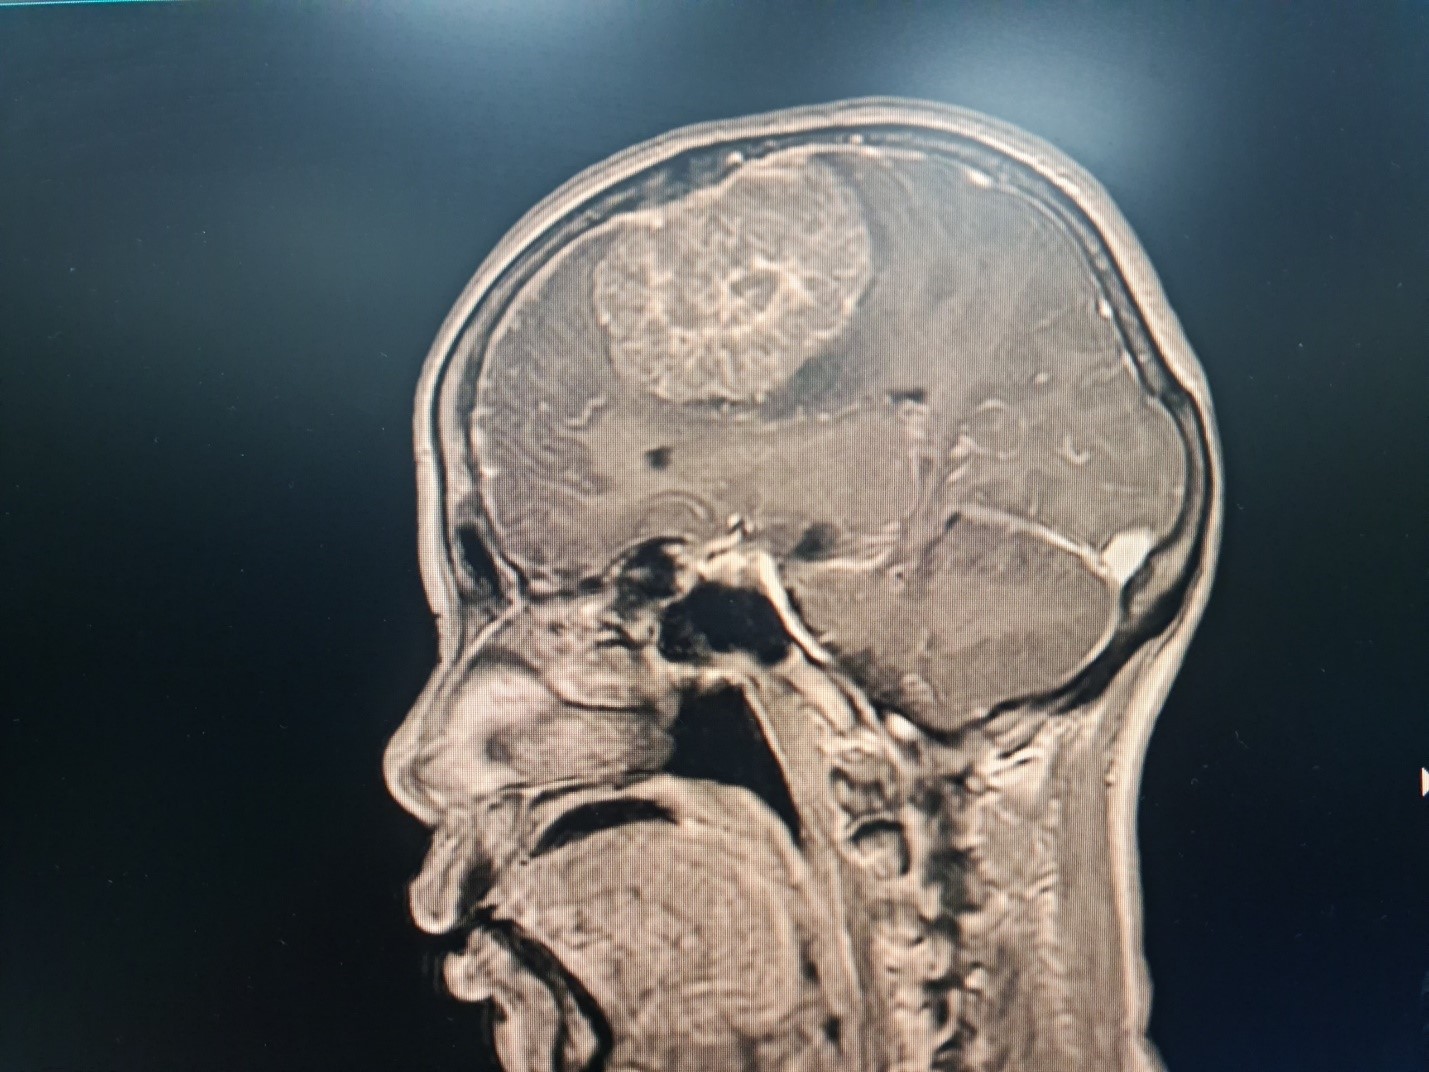

Kết quả thăm khám và chụp MRI sọ não có tiêm thuốc tương phản tại Bệnh viện Đa khoa tỉnh Thanh Hoá phát hiện bệnh nhân có khối u màng não bán cầu phải, kích thước lớn 7x8cm. Khối u nằm sát, xâm lấn xoang tĩnh mạch dọc giữa và 1 phần xương sọ, gây chèn ép ¼ não và phù não xung quanh. Bệnh nhân và người nhà được các bác sĩ tư vấn cần sớm phẫu thuật điều trị, vì khối u lớn sẽ chèn ép, gây nhiều tổn thương nghiêm trọng đến nhiều chức năng của cơ thể bệnh nhân như: vận động, thị giác, nhận thức,… và thậm chí có thể tử vong.

Hình ảnh khối u của bệnh nhân trên phim chụp MRI sọ não tiêm chất tương phản